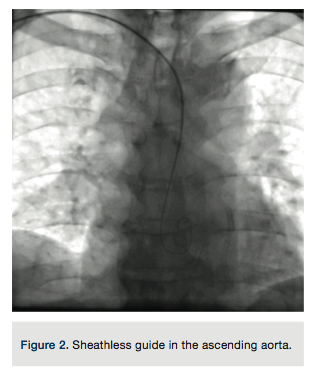

A 4 French (Fr) Glidesheath (Terumo Corporation) was inserted in the right radial artery and a vasodilator cocktail of 2.5 mg verapamil and 100 micrograms of nitroglycerin were given via the sheath. Since this was to be a planned chronic total occlusion (CTO) intervention, 5,000 units of heparin were given via an intravenous route. The 4 Fr introducer was exchanged out for a 6.5 PB4.0 Asahi sheathless guide (Asahi Intecc) (Figures 1-2). A control angiogram of the left coronary (Figure 3) reveals a total occlusion in the distal circumflex artery.